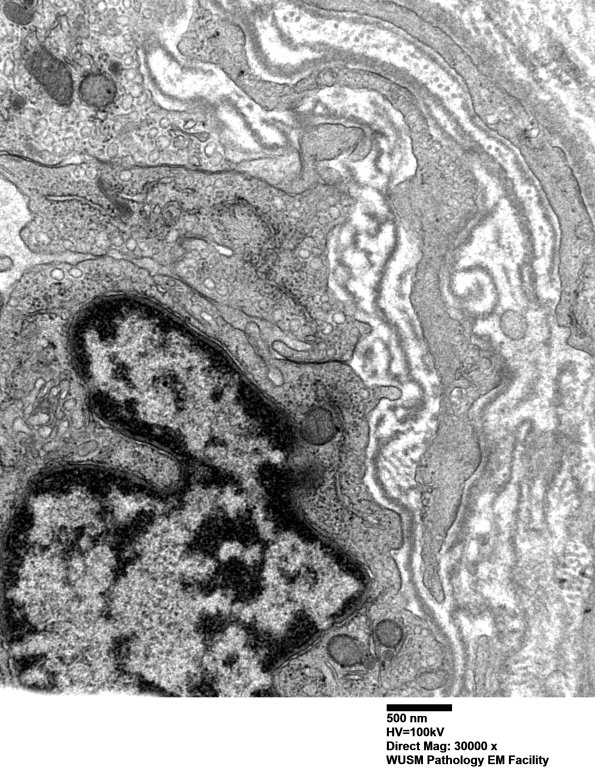

Washington University Experience | VASCULAR | Hypoxia-Ischemia, fetal-neonatal | White Matter | 16B10 (Case 16) HIEM EM031 - Copy

16B10 (Case 16) HIEM EM031 - Copy